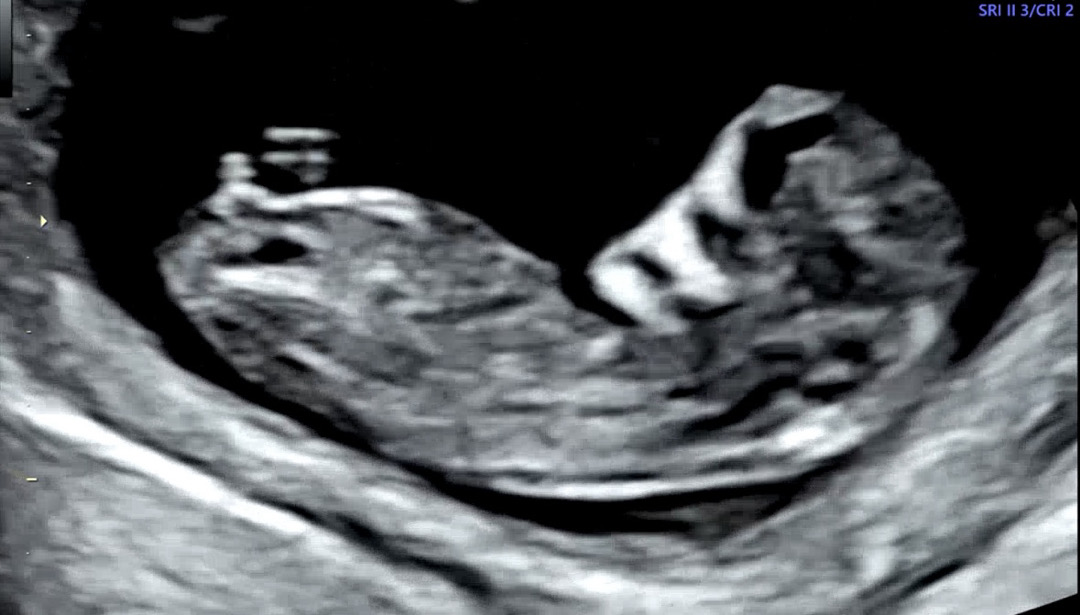

11주차 성별 봐주세요!

오늘 초음파 보고 왔는데 아들일까요?